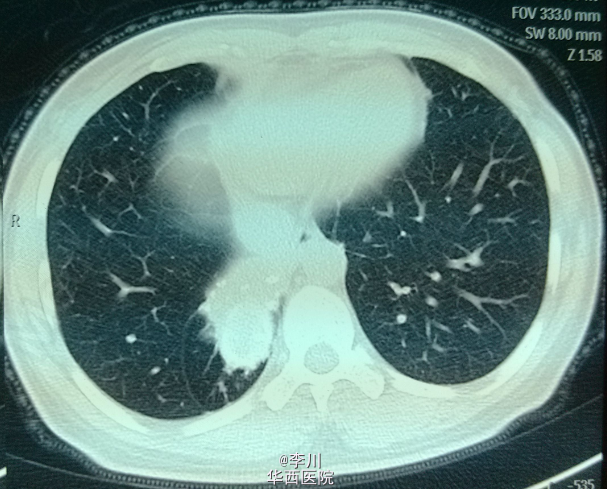

患者为43岁女性,因“咳嗽咳痰伴胸闷、气紧4+月”入院。患者4+月前无明显诱因出现咳嗽咳痰,伴胸闷气紧,外院行相关检查后诊断为“肺炎”,予抗感染治疗20天后无明显缓解。遂于我院就诊。

查体:双侧锁骨上淋巴结未触及肿大。视:双侧胸廓对称,未见畸形,双肺呼吸动度对称。触:触觉语颤对称,未触及胸膜摩擦感,心尖搏动位于左锁骨中线,未见异常搏动。叩:双肺叩清音,双肺活动度对称。听:右下肺肺呼吸音低,未闻及干湿罗音及胸膜摩擦音,心前区未及病理性杂音。我院胸部CT示:右肺下叶不规则片团影,伴右肺下叶不张。

术前诊断为右下肺结核球。于全麻下行右肺下叶切除术。术中取出病灶,可见干酪样坏死。术后病理确诊为肺结核病灶。术后患者恢复可,仍需抗痨治疗。